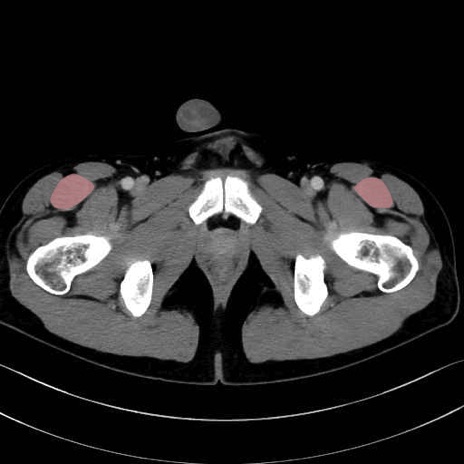

大腿直筋 (Rectus femoris)